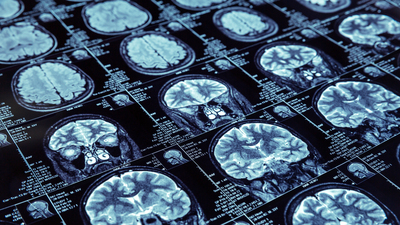

Sağlık bilişimi alanında MR, PET gibi radyolojik görüntülerin bilgisayar ortamında modellemesine dayalı tanı sistemleri geliştirmeye dönük çalışmaların ilerlediğini ifade eden Son, "Böylece klinikte, doktorların hastalığın ayırıcı tanısına destek olabilecek ön araştırmalar yapılıyor" diye konuştu